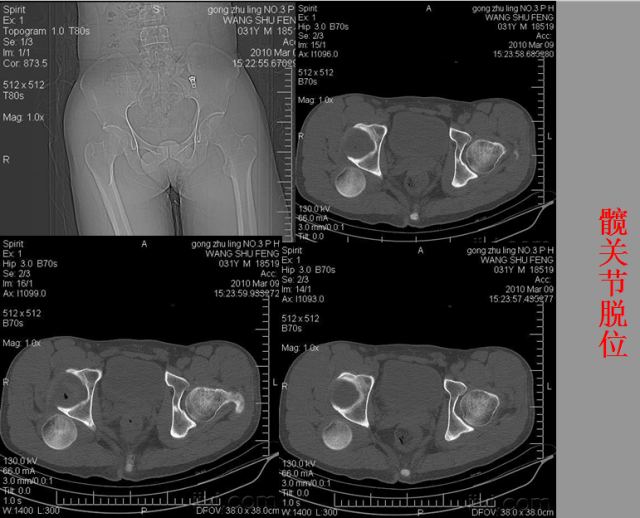

关节脱位篇

02

定义:关节脱位是暴力、关节感染、附近软组织挛缩或先天骨发育障碍造成的关节对位关系部分或完全脱离,即为半脱位或脱位。临床上以创伤性脱位*常见。